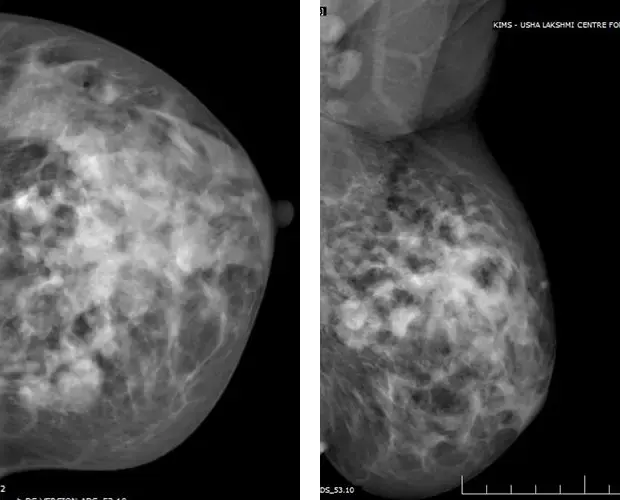

A & B) Left breast MLO and CC views showing irregular medium to high density mass in upper and outer quadrant of left breast ( straight white arrows) with associated interstitial thickening ( curved white arrow), ductal dilatation, skin thickening and retraction of the nipple (red arrow).

Left breast CC and MLO views

A) & B) Left breast CC and MLO view showing large asymmetric density in upper and central quadrant of left breast (black arrows) with associated interstitial thickening (white arrow) and architectural distortion .Multiple mass like areas seen in the medial and lower quadrant (red arrows) of left breast